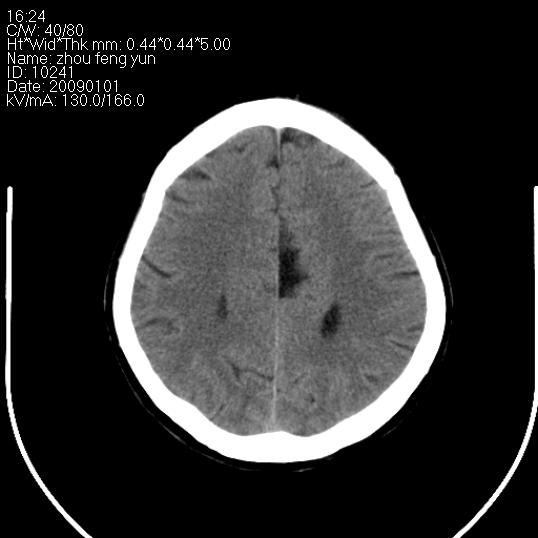

以下是引用hhcckk在2009-1-1 16:39:00的发言:[br]胼胝体嘴、膝部及部分体部发育不全,为囊状影替代,两侧侧脑室分离,脑室后角扩张[br][br]诊断:胼胝体发育不良[br][br]胼胝体发育不良(dysgenesis of the corpus callosum)是最常见的颅脑畸形,是胚胎期背部中线结构发育不良的一种形式。主要包括胼胝体缺如和部分缺如。胼胝体发育不良还可合并其他畸形,如胼胝体脂肪瘤、蛛网膜囊肿、脑膨出、chiari畸形、灰质异位症、脑回畸形等。[br][br]ct诊断要点:[br]1. ct横断扫描可见两侧侧脑室明显分离,脑室后角扩张,形成典型的蝙蝠翼状侧脑室外形。[br]2. 第三脑室扩大并向上插入两侧脑室体部之间,严重者第三脑室可上移到两侧大脑半球纵裂的顶部。在ct冠状扫描位显示更清。[br]4. 胼胝体畸形常伴有脂肪瘤,可测到其特征性脂肪密度。部分脂肪瘤的边缘可出现线样钙化[br]